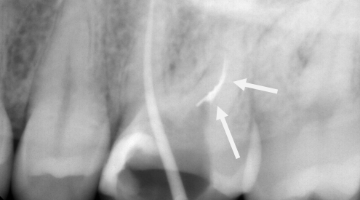

By 2:22 p.m., I was taking periapical x-rays with the gutta-percha to check my working lengths and evaluate the separated files. The x-ray showed that my access wasn’t as open as I originally thought it to be. The canal curved in two places, which caused the file separations. At this point I had two separated files—the 0.1 Twisted File (TF) file and the 15 mm hand file I had used to bypass the canal.

I proceeded to bypass the separated files with a 10 c-file. The apex locator still wasn’t giving me a reading. I was ready to obturate the canal, leaving all the extra metal as fill. Upon drying the canal with paper points, I noticed the paper point disappeared immediately toward the buccal. I took a step back to remove the buccal wall for better access. At this point, I was able to visualize the DB canal much better and was able to remove both of the separated instruments.